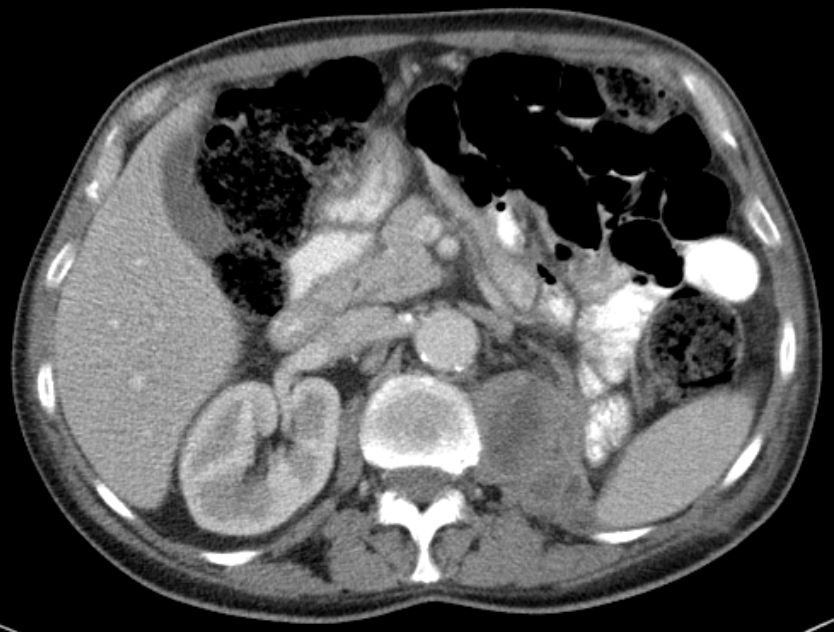

61-jähriger Mann bei dem notfallmäßig eine Tumornephrektomie links wegen Sepsis und nekrotisch zerfallendem, infiziert rupturiertem NZK links cT3b pM0 M0 G2 durchgeführt wurde. Makroskopie: 15 x 9 x 10 cm großes Nephrektomiepräparat. Im Zentrum überwiegend im Hilusbereich entwickelt, ein stark nekrotisch zerfallender, 8 cm großer Tumor.

Mikroskopie: Der Tumor zeigt papilläre, teilweise tubuläre Strukturen.

Die Einzelzellen enthalten vergrößerte hyperchromatische Zellkerne mit prominenten Nukleolen.

Das Zytoplasma ist teilweise klar, teilweise schwach eosinrot angefärbt.

Teilweise erkennt man Tumoranteile mit girlandenförmigen Proliferaten.

Immunhistochemie: z.T positiv mit CD 10. Herdförmig kräftig positive Reaktion mit Zytokeratin 7 und Vimentin. CD 117, Melan A und HMB 45 negativ.

5 Monate später Rezidiv. Th.:Pazopanib